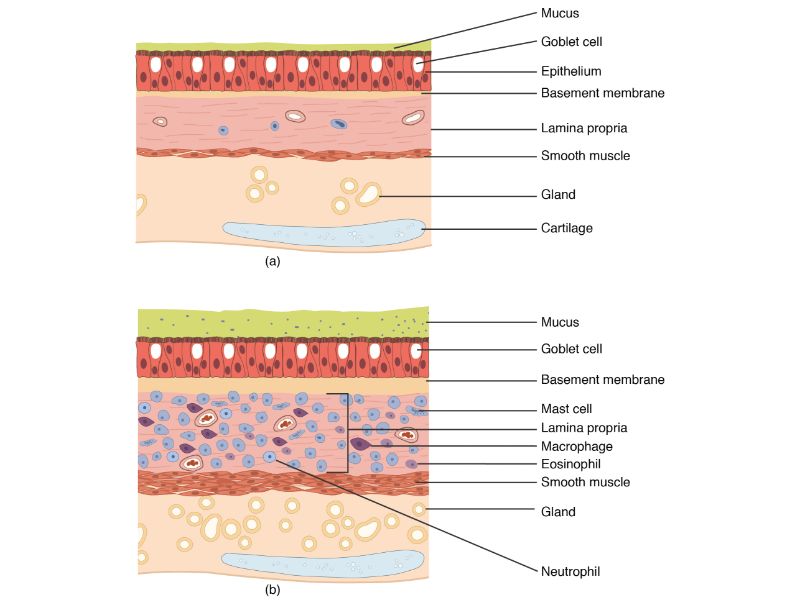

Respiratory epithelium

- Pseudostratified

- Ciliated

- Columnar

- Epithelium with

- 4 Cells

- Ciliated columnar cells

- Non-ciliated columnar cells

- Goblet cells

- Basal cells